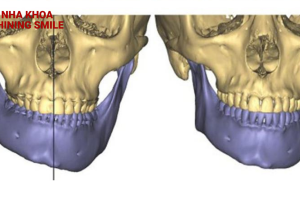

Quy Trình Niềng Răng Móm Chi Tiết: Từ A Đến Z

Quy trình niềng răng móm bao gồm nhiều bước quan trọng để đạt được kết quả mong muốn. Hiểu rõ các bước trong quy trình này sẽ giúp người bệnh chủ động tham gia và đạt được hiệu quả điều trị tốt nhất. Cùng Shining Smile tìm hiểu qua bài viết sau đây.